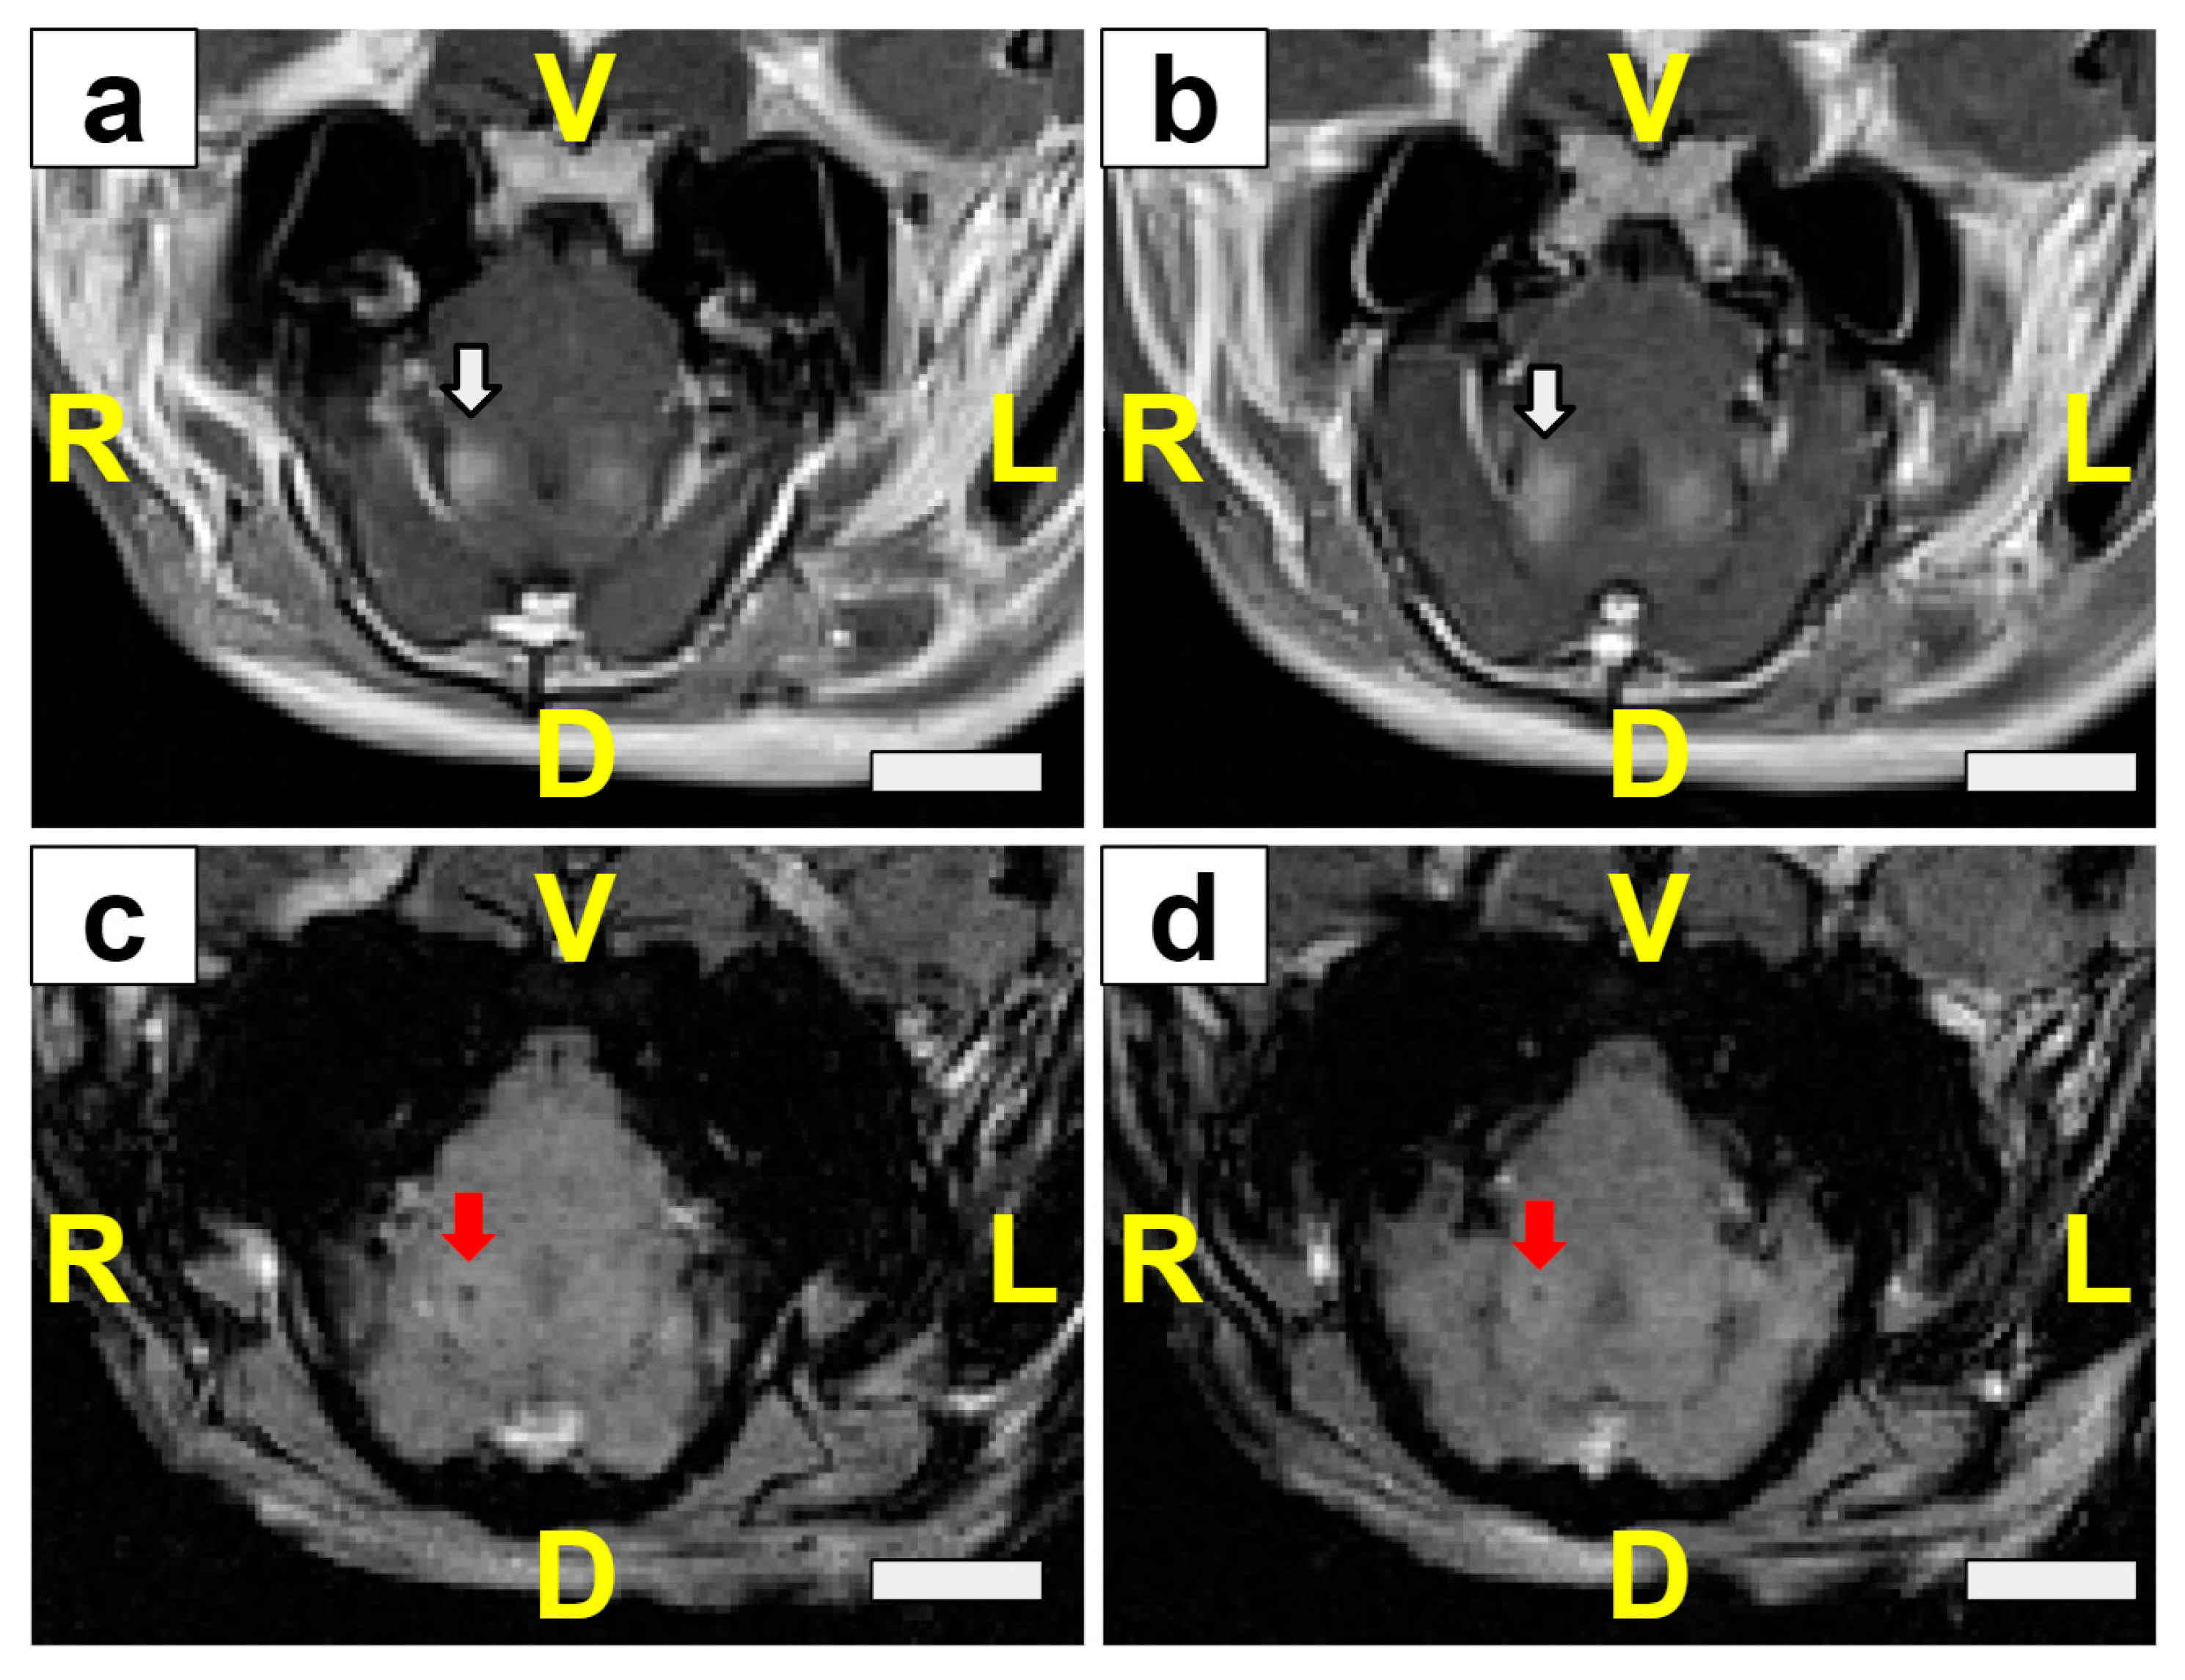

3.4. T2*w MRI Rarely Displayed Signal Hypointensities